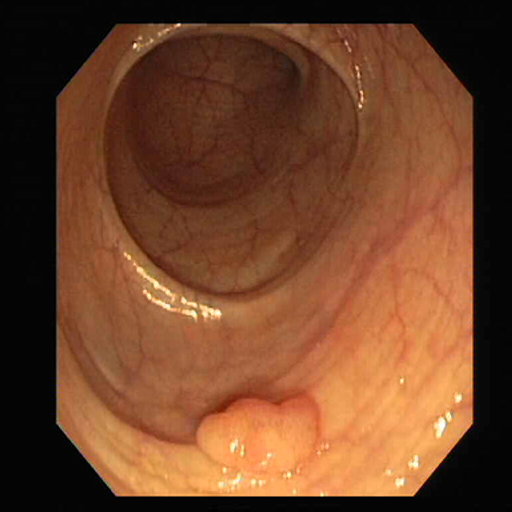

Global health faces a significant burden from colorectal cancer (CRC), the second most commonly diagnosed cancer and third leading cause of cancer-related mortality [1]. Research indicates that approximately 95% of CRC cases originate from colorectal adenomatous polyps [2]. While the overall survival rate for CRC is 63%, early detection and treatment at a localized stage can significantly improve this rate to 91% [2, 3]. Fig. 1(a) summarize the statistics for polyps by age and gender. However, survival drops to 14% when the cancer metastasizes to distant organs. Consequently, early polyp detection and treatment are crucial for CRC prevention and reducing mortality rates. However, the manual detection process is labor-intensive, and variability in clinician expertise can lead to overlooking polyps during colonoscopy.

Automated gastrointestinal polyp segmentation presents significant challenges due to various factors illustrated in Fig. 1(b). Uneven illumination from body fluid reflection can degrade image quality, while noise artifacts like surgical instruments and intestinal contents complicate segmentation. Low contrast between tissues hinders accurate polyp localization and identification. Additionally, residual stool and digestive fluids can obscure internal tissues, making differentiation difficult. Polyp boundaries are blurred or unclear due to similar appearance patterns. Furthermore, inter-patient variability and diverse polyp types exhibit various colors and textures. Moreover, an imbalance in pixel distribution, as shown in Fig. 1(c), with the background area often exceeding the polyp area, introduces noise that affects segmentation performance.

Fig. 7 offers qualitative validation, showcasing MNet-SAt’s superior polyp mask generation compared to baselines across four cases. This qualitative superiority aligns with the previously established quantitative results. In the case of small polyps (first and fifth rows), all baseline methods initially appear to produce satisfactory visual results. However, upon closer inspection, they fail to maintain fine boundary details. Our framework excels in preserving polyp anatomy and topology for medium and large polyps, significantly outperforming the baseline methods. Notably, even in multiple polyps, our framework successfully captures more polyps and approximates the ground truth more closely. The primary reason for this superior performance is the EGFE module, which effectively eliminates noise in conjunction with the HMAtt module, resulting in a few false positives. Our analysis reinforces MNet-SAt’s effectiveness in handling challenging polyp scenarios (small, medium, large-scale, and multi-polyps) while suppressing non-regions of interest.